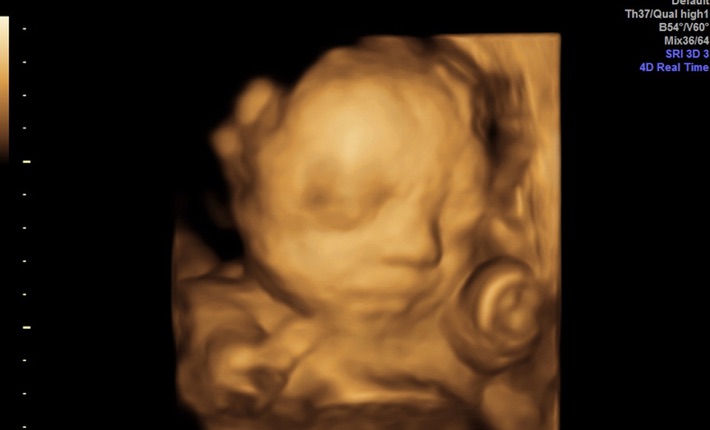

(IINews) - Sie liefern spektakuläre Bilder vom werdenden Leben und lösen zunehmend die herkömmliche zweidimensionale Darstellung bei Untersuchungen im Rahmen der Geburtshilfe ab. Zugleich eröffnen sich mit der Anwendung der 3D/4D Ultraschalltechnik ganz neue diagnostische Möglichkeiten. Dreidimensionale Ultraschallsonden liefern Bilder des Kindes wie auf einem Foto. Gesichtszüge und Körper werden erkennbar dargestellt. Bei vierdimensionalen Ultraschallsonden lassen sich zudem Bewegungen des Kindes in Echtzeit zeigen, Mimik und Gesichtsausdrücke werden abgebildet. Mithilfe dieser modernen Sonden sind exakte Überprüfungen des Körpervolumens und eine Erfassung der Blutgefäße und Organe des Fötus möglich. Bilder können abgespeichert und sogar auf das Handy der Eltern übertragen werden. "Um diese modernen Sonden fachgerecht warten und reparieren zu können, braucht es ausgewiesenen Sachverstand", betont Monika Wüster, Geschäftsführerin von Medi-ManAge mit Sitz in Mainz.

Mit 3D/4D Ultraschallgeräten lassen sich Babys im Mutterleib nicht einfach nur abbilden. Die diagnostischen Fähigkeiten dieser Geräte gehen weit darüber hinaus. Sie verhelfen dem Gynäkologen zu einer Bewertung des Verhaltens des Fötus und zu Rückschlüssen auf die Entwicklung seines zentralen Nervensystems. Hirnfunktionsstörungen lassen sich mithilfe dieser speziellen Ultraschallsonden frühzeitig erkennen. Zugleich eröffnen sich Chancen einer Behandlung bereits im Mutterleib. "Die reibungslose und verlässliche Funktionsweise von 3D/4D Ultraschallsonden ist eine grundlegende Voraussetzung für eine gesicherte Diagnostik", betont Monika Wüster.